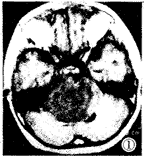

图1-3 女性,5岁,脑干明显增大膨突,横断面T1W低信号(图1),T2W高信号(图3),无明显强化(图2),肿块向前包绕基底动脉,向后推移第四脑室。图4-6 女性,6岁,横断面T1W低信号(图4),矢状面T1W增强(图5), 横断面T1W增强(图6),片状不均匀强化灶中见结节样强化。图7 男 性,6岁,横断面T1W增强,肿块环状强化呈葫芦形,中央低信号灶不强化。图8 女性,2岁,矢状面T2W,肿块向后压迫中脑导水管,第三脑室、侧脑室积水明显。

MRI:鉴于无颅骨伪影和多方位成像特点,MR是目前诊断胶质瘤和准确定位的最好方法,对于治疗计划的制定和随访有很大帮助,特征性MR表现为脑干胶质瘤呈膨胀性生长(图1~3),多为实质性,在T2加权图像上显示最为清楚,为明显高信号(图3),在T1加权图像上为低信号或低、等混合信号(图4),注射GD-DTPA后多数病灶 明显增强,少数无明显增强(图1~2),强化方式有:弥漫型(图未列出)、结节型(图4 ~6),沿着肿瘤边缘或囊变坏死区呈环状(图7)。肿瘤边界多较清楚,周围脑组织水肿多 较轻或不明显,肿瘤内部可发生小囊变或小出血灶,肿瘤向前生长包埋基底动脉(图1~3) ,部分脑干胶质瘤可位于中脑导水管附近,虽然较小,但可造成对中脑导水管的压迫,而继 发脑积水[3](图8),MRI较CT能更好地明确占位性病变的性质、部位、范围。